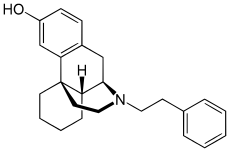

The pharmacodynamic response to an opioid depends upon the receptor to which it binds, its affinity for that receptor, and whether the opioid is an agonist or an antagonist. For example, the supraspinal analgesic properties of the opioid agonist morphine are mediated by activation of the μ1 receptor; respiratory depression and physical dependence by the μ2 receptor; and sedation and spinal analgesia by the κ receptor. Each group of opioid receptors elicits a distinct set of neurological responses, with the receptor subtypes (such as μ1 and μ2 for example) providing even more [measurably] specific responses. Unique to each opioid is its distinct binding affinity to the various classes of opioid receptors (e.g. the μ, κ, and δ opioid receptors are activated at different magnitudes according to the specific receptor binding affinities of the opioid). For example, the opiate alkaloid morphine exhibits high-affinity binding to the μ-opioid receptor, while ketazocine exhibits high affinity to ĸ receptors. It is this combinatorial mechanism that allows for such a wide class of opioids and molecular designs to exist, each with its own unique effect profile. Their individual molecular structure is also responsible for their different duration of action, whereby metabolic breakdown (such as N-dealkylation) is responsible for opioid metabolism.

Several semi-synthetic opioids were developed in Germany in the 1910s. The first, oxymorphone, was synthesized from thebaine, an opioid alkaloid in opium poppies, in 1914.[228] Next, Martin Freund and Edmund Speyer developed oxycodone, also from thebaine, at the University of Frankfurt in 1916.[229] In 1920, hydrocodone was prepared by Carl Mannich and Helene Löwenheim, deriving it from codeine. In 1924, hydromorphone was synthesized by adding hydrogen to morphine. Etorphine was synthesized in 1960, from the oripavine in opium poppy straw. Buprenorphine was discovered in 1972.[228]

Morphinan derivatives